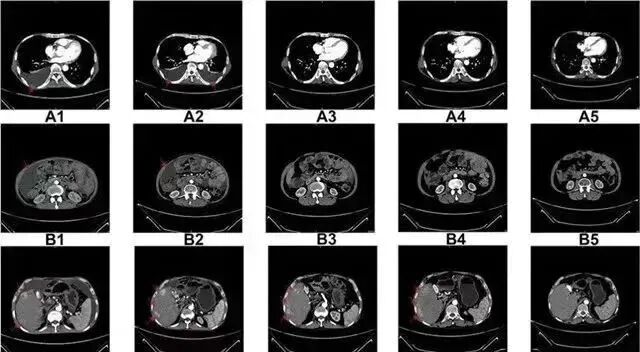

△  NK细胞治疗前和治疗期间的CT扫描结果

案例1:国外知名杂志《Oncotargets and Therapy》的一例试验报告显示:NK细胞疗法让晚期肝癌患者肿瘤显著缩小,从生存期仅3个月到超过4年!

案例2:国内一名60岁的卵巢癌晚期患者,在接受了体外扩增,高度活化的同种异体NK细胞的治疗后,CA125水平从11,270降至580,所有腹水都消失了。此外,CT扫描的肿块体积减小,并且没有出现副作用。